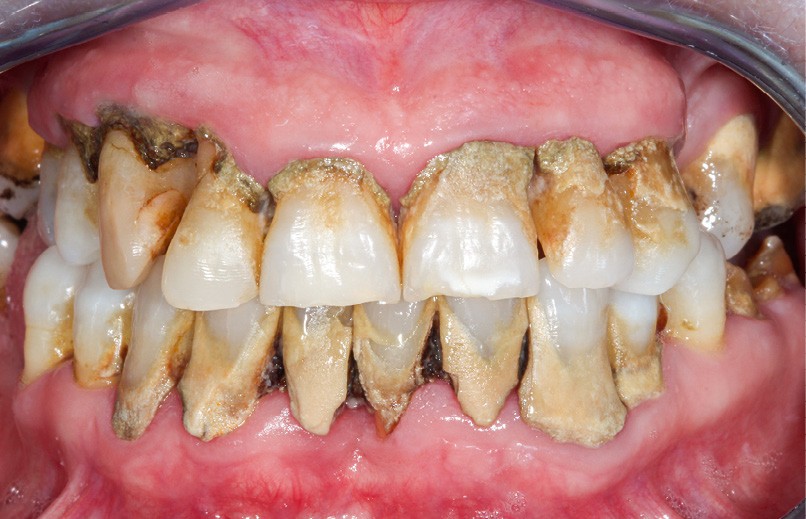

• Extrinsèques : liées aux colorations de surface (tabac, café, thé, vin rouge, alimentation, tartre ou plaque bactérienne) (fig. 4).